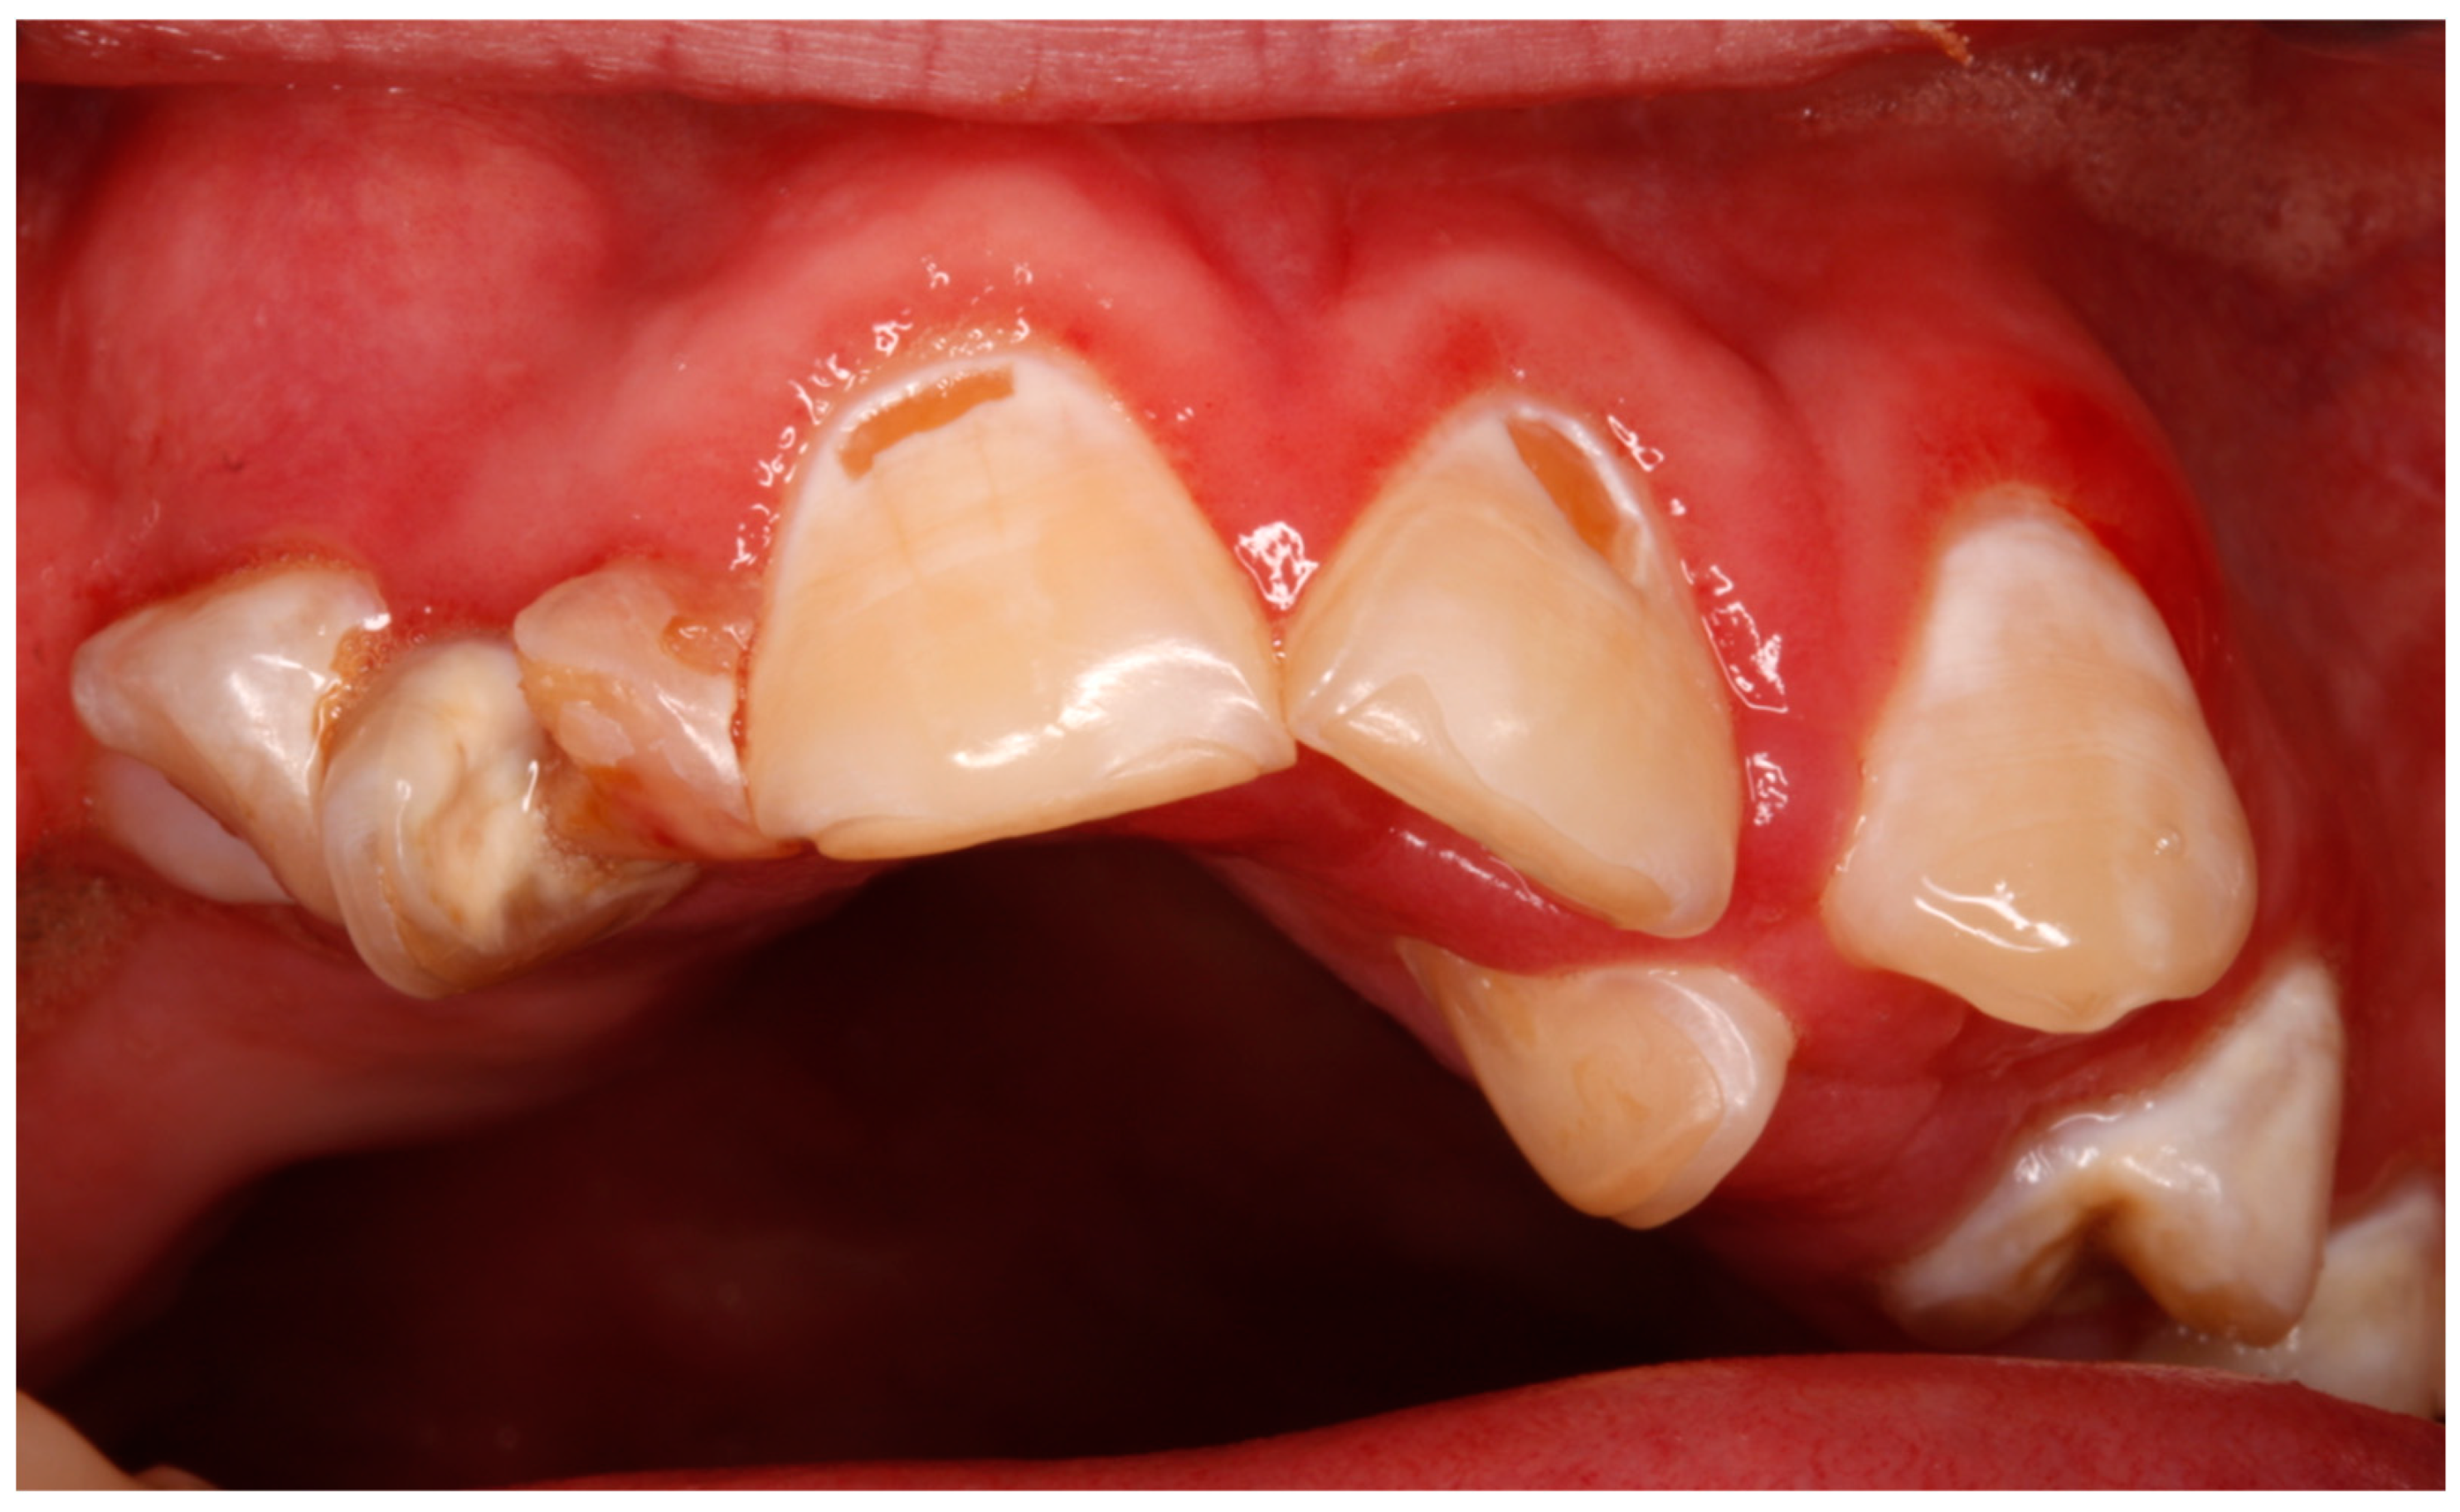

| Cavities | 8 (57.1) | |

| Bruxism/attrition | 4 (28.5) | |

| Dental malposition | 2 (14.2) | |

| Enamel hypoplasia | 2 (14.2) | |

| Dental fracture | 1 (7.1) | |